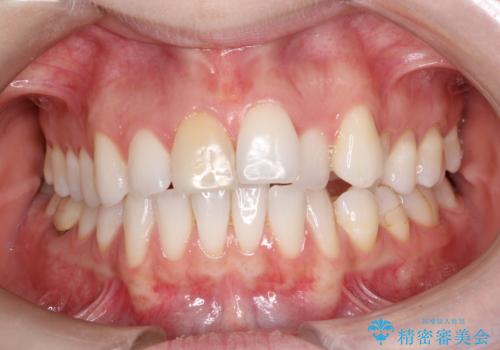

インビザラインで出っ歯を改善する 抜歯をしないinvisalign治療

- 非抜歯・遠心移動による前突の改善をマウスピースにて計画した。

非抜歯矯正の場合、大きく前歯を下げることはできませんが、奥歯の遠心移動や歯のサイズダウンにより歯軸を立て、見かけ上の出っ歯感をある程度改善することができます。